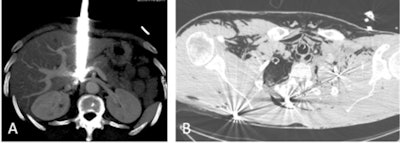

The reference imaging modality is CT. With negative and positive predictive values greater than 80% or even 90% for a serious underlying thoracic or abdominal lesion, CT will make it possible to direct the management of the patient in an emergency and decide on conservative management or surgical/interventional treatment.

The usual diagnostic protocol should include arterial acquisition of the thorax, abdomen, and pelvis, followed by venous acquisition of the abdomen and pelvis. For "simple" penetrating traumas (knives in particular), cases in which the lesional mechanism is known, there are no deceleration lesions, and ballistics for the lesions are suggested by the clinic (visible entry point, possible exit point in the event of a gunshot wound), a more targeted CT scan could be considered.